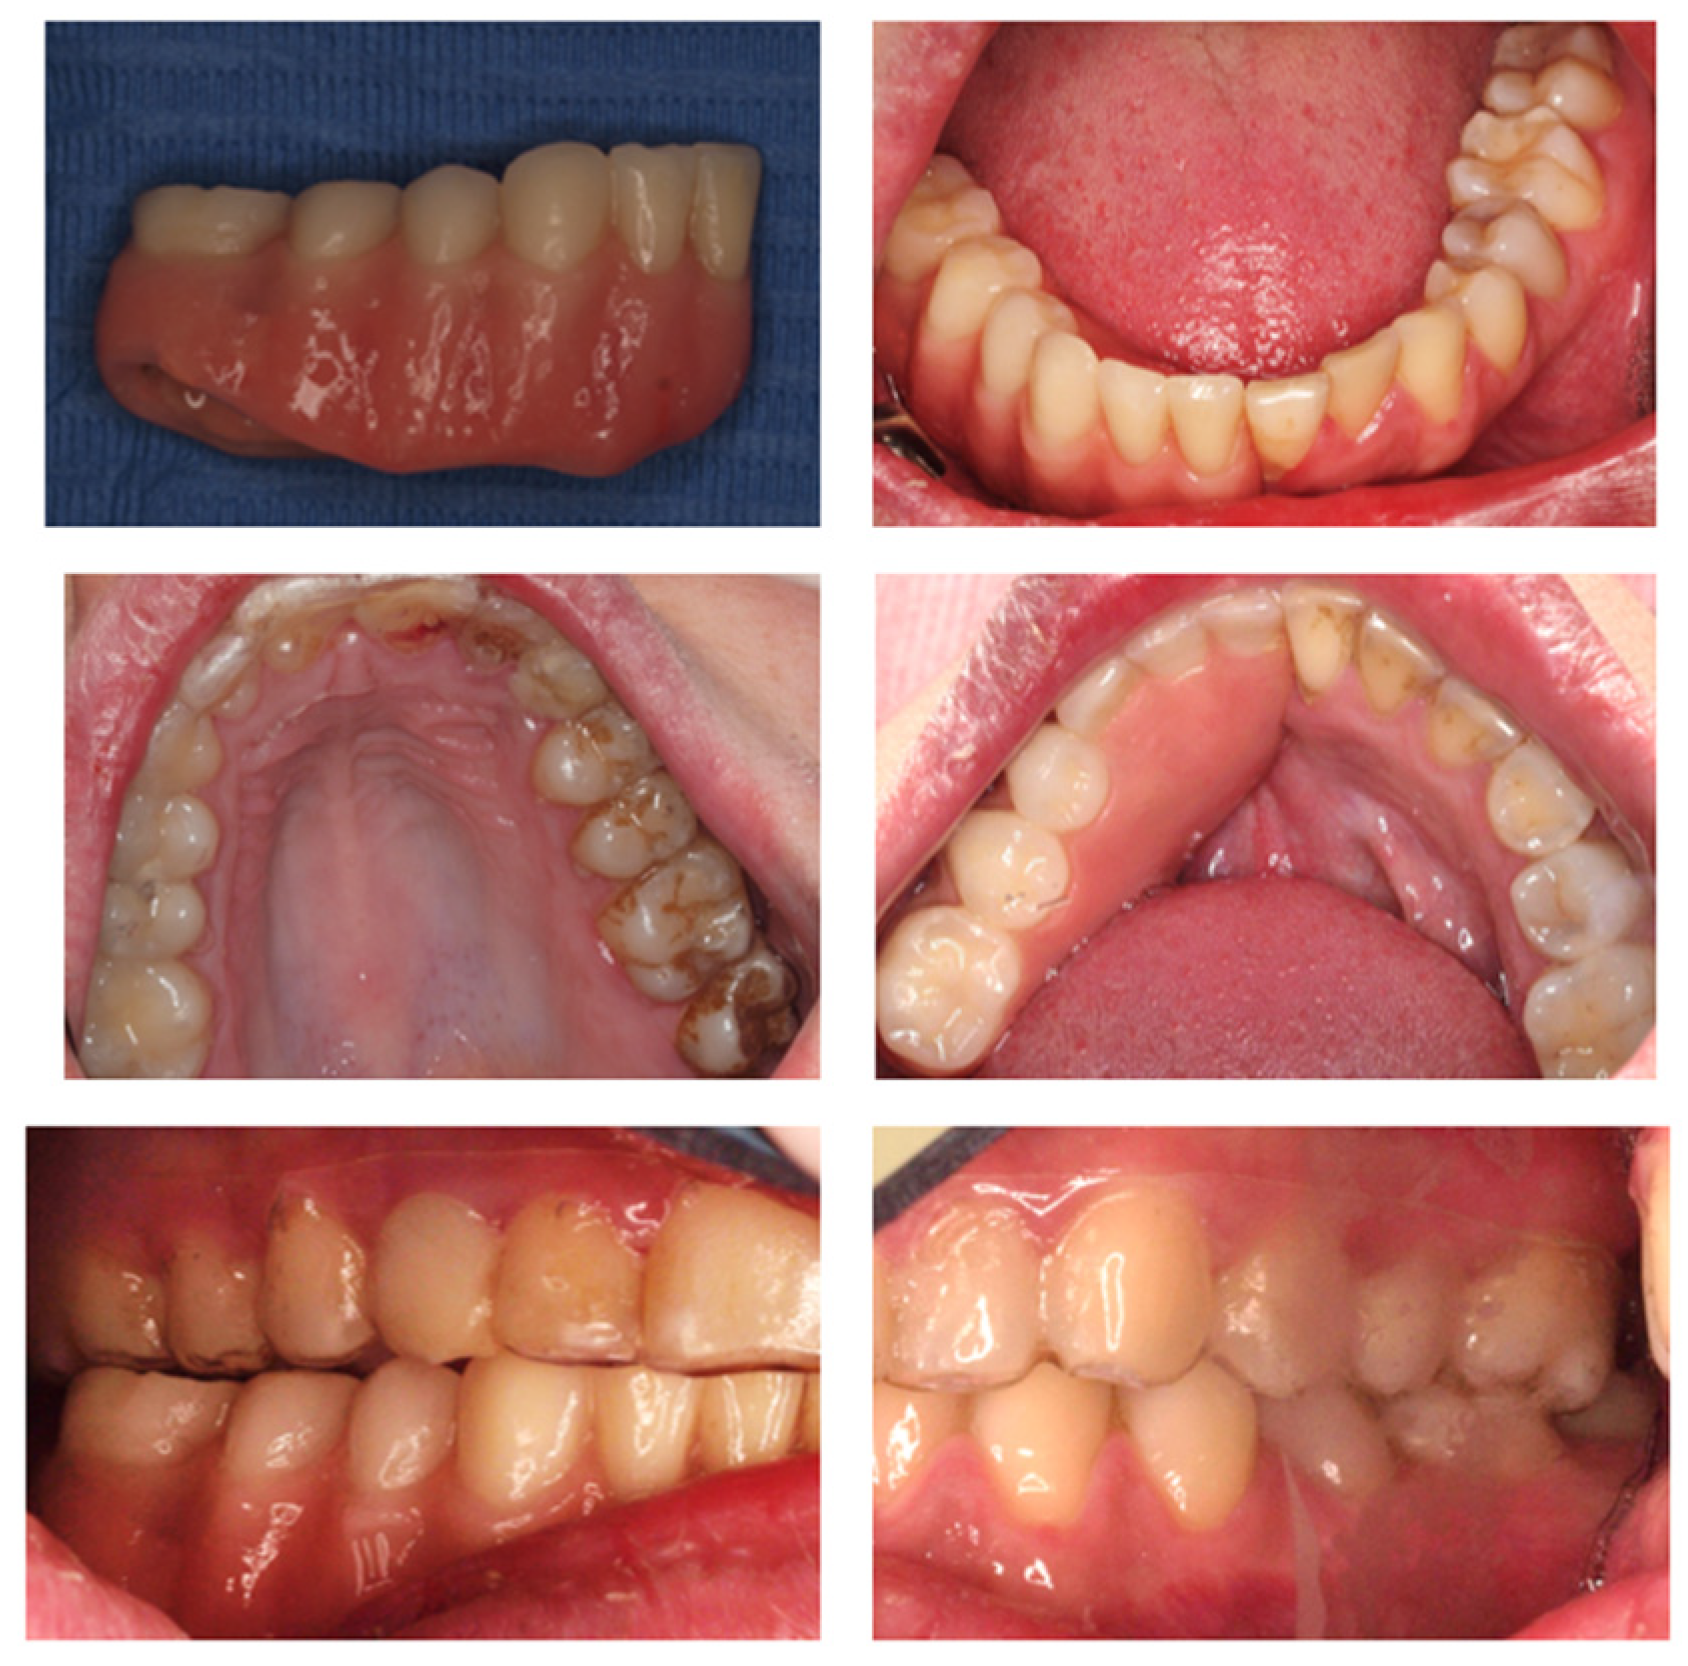

2. Materials and Methods

Clinical Case

| 2022 | Periodontal control |

| 2022–2023 | Complementary exams and planification |

| 2023 | Surgery of 4 implants in the jaw |

| 2023–2024 | Start with rehabilitation phase |

| 2024 | Prosthetic installation |